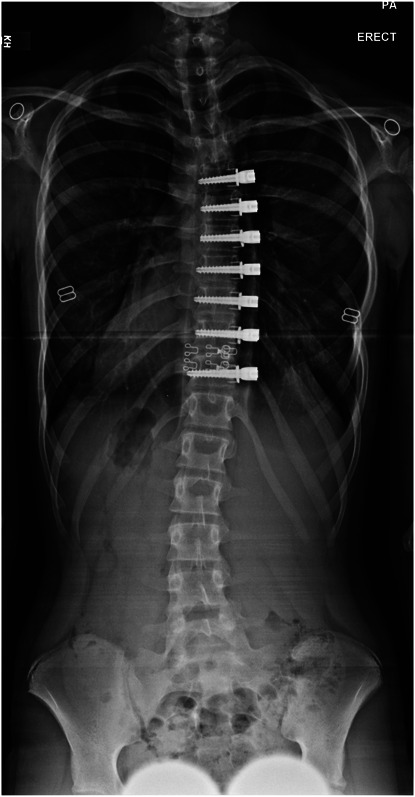

背景:椎体栓系术(VBT)为特发性脊柱侧凸患者提供了另一种治疗方法。我们提交了最终的食品和药物管理局VBT研究器械豁免(IDE)研究结果。方法:回顾性分析2011 - 2015年间Lenke IA/B型曲线患者行VBT的临床资料。前瞻性地收集临床、影像学、围手术期和并发症资料。结果:57例患者入组,平均年龄12.4±1.3岁,随访6.6±1.6年(范围3.0 ~ 10.2年)。术前胸椎Cobb角为40.4±6.8°,2年后矫正为14.5±9.0°,最后随访时略微回落至22.1±12.4°。Sanders和Risser的中位数分别为3和0。最后随访时,71%(39/56)患者骨骼曲线≤30°,98%(55/56)患者骨骼成熟。没有严重的神经或肺部并发症。然而,10名患者需要13次翻修;2 .需要转化为核聚变。预测用力呼气量和用力肺活量的百分比在最后随访时分别从85%和87%下降到80%和82%。结论:这些最终的IDE结果强调VBT是一种安全、有效的治疗骨骼未成熟的特发性脊柱侧凸患者的方法。然而,并发症和翻修率仍然令人担忧,患者应该得到适当的建议。证据等级:三级。有关证据水平的完整描述,请参见作者说明。

Results: Fifty-seven patients (mean age 12.4 ± 1.3 years) were enrolled and followed for 6.6 ± 1.6 years (range: 3.0-10.2 years). Thoracic Cobb angle measured 40.4 ± 6.8° preoperatively with correction to 14.5 ± 9.0° at 2 years and slight regression to 22.1 ± 12.4° at last follow-up. Median Sanders and Risser were 3 and 0, respectively. At last follow-up, 71% of patients (39/56) had curves ≤30° and 98% (55/56) had achieved skeletal maturity. There were no major neurologic or pulmonary complications. However, 10 patients required 13 revisions; 2 required conversion to fusion. Percent predicted forced expiratory volume and forced vital capacity dropped from 85% and 87%, respectively, to 80% and 82% at the final follow-up.